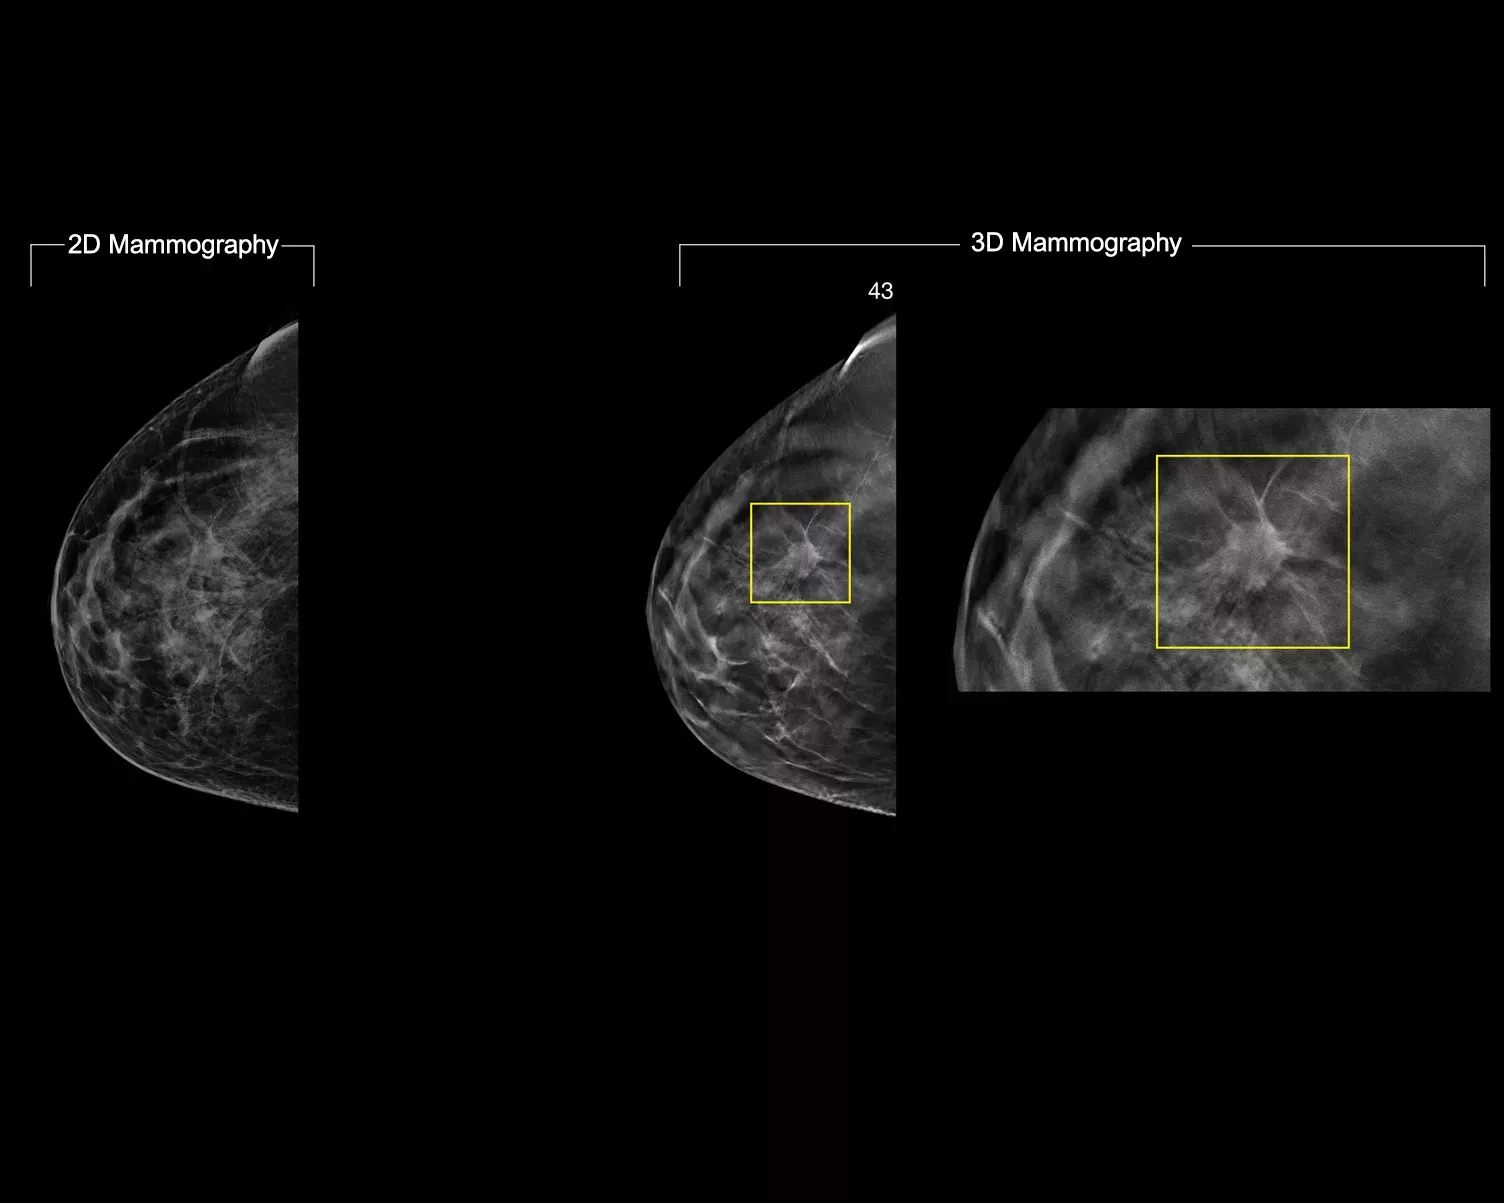

3DQuorum-teknologien bruger Genius AI™ drevne analyser til at rekonstruere højopløselige 3D Mammography™ data på en unik måde for at producere 6 mm SmartSlices. Det reducerer antallet af billeder, der skal gennemgås, og forkorter dermed læsetiden – uden at gå på kompromis med billedkvalitet, sensitivitet eller nøjagtighed.2,3 Med vores nyeste innovation kan du forkorte læsetiden med en time om dagen.2,3*

Genius AI-analyse identificerer områder af interesse og bevarer vigtige funktioner under dannelsen af SmartSlices.2 De 6 mm SmartSlices med 3 mm overlap sikrer, at der ikke går data tabt, og at der er kontinuitet i scrollingen.4-6

Når man læser SmartSlices i stedet for 1 mm-snit, reduceres antallet af 3D™ billeder, der skal gennemgås, med to tredjedele.4-6 Dette sparer i gennemsnit 1 time pr. dag i billedfortolkningstid.3